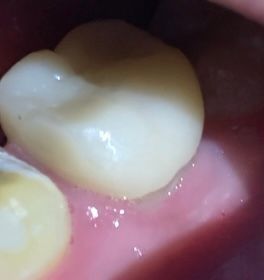

신경치료 한 이랑 잇몸 부분 회색 선?이 보입니다.

예전에 신경치료 후 크라운(?)으로 씌운 곳이랑 잇몸 부분에 회색 선 같은게 보입니다.

잇몸이 조금 주저 앉아서 안에 보철? 이가 보이는 건가요?

교정을 해서 예전보다 잇몸이 살짝 내려 앉은 느낌이 전체적으로 있는 거 같습니다.

회색선으로 보인다는 부분은 실제로 보철을 씌운 치아 안에 부분입니다. 사진 상으로 큰 문제가 되지 않습니다. 이러한 경우는 대부분 잇몸이 내려가거나 보철을 할 때 치은연상 마진을 한다면 지금처럼 보일 수 있습니다. 특별히 음식물이 많이 고이거나 해당 부분에 충치 등이 생기지 않는다면 걱정하지 않아도 되는 부분입니다.

잇몸이 퇴축되면서 틈이 보이는 것으로 보입니다. 관리만 잘 해주신다면 문제가 되진 않습니다.

잇몸이 내려가면서 치아가 약간 보이는거 같습니다. 큰 문제가 잇는건 아니니 관리만 잘해주시면됩니다.

간이 지나면서 크라운과 잇몸 사이의 간격이 생길 수 있으며, 이로인해 경계부분이 노출될수 있습니다. 통증이나 시림증상이 있지 않은 경우 문제가 되지 않으나, 만약 불편감이 있는 경우 치과에 방문하여 상태를 확인하고, 빠른 조치를 받길 권합니다.

처음 크라운을 제작했을때보다 잇몸이 퇴축되면서 치아 부위가 드러난 것입니다. 크라운 기능상에는 특별히 큰 문제는 없습니다. 신경치료가 된 치아이므로 시리거나 하지는 않을 것입니다. 해당 부위 음식물, 치태가 끼지 않도록 관리만 잘해주면 굳이 교체안해주고 써도 되나 신경쓰이신다면 기존 크라운 뜯고 재제작은 할 수 있습니다.